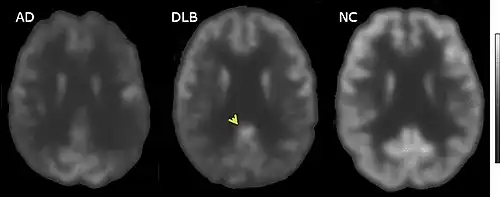

Direct laboratory-measurable biomarkers for DLB diagnosis are not known, but several indirect methods can lend further evidence for diagnosis.[24] The indicative diagnostic biomarkers are: reduced dopamine transporter uptake in the basal ganglia shown on PET or SPECT imaging; low uptake of 123iodine-metaiodobenzylguanidine (123I-MIBG) shown on myocardial scintigraphy; and loss of atonia during REM sleep evidenced on polysomnography. Supportive diagnostic biomarkers (from PET, SPECT, CT, or MRI brain imaging studies or EEG monitoring[121]) are: lack of damage to medial temporal lobe (damage is more likely in Alzheimer's disease[113]); reduced occipital activity; and prominent slow-wave activity on EEG.[24]

PET or SPECT imaging can be used to detect reduced dopamine transporter uptake and distinguish AD from DLB.[56][144] Severe atrophy of the hippocampus is more typical of AD than DLB.[145] Before dementia develops (during the mild cognitive impairment phase), MRI scans show normal hippocampal volume. After dementia develops, MRI shows more atrophy among individuals with AD, and a slower reduction in volume over time among people with DLB than those with AD.[32] Compared to people with AD, FDG-PET brain scans in people with DLB often show a cingulate island sign.[32]